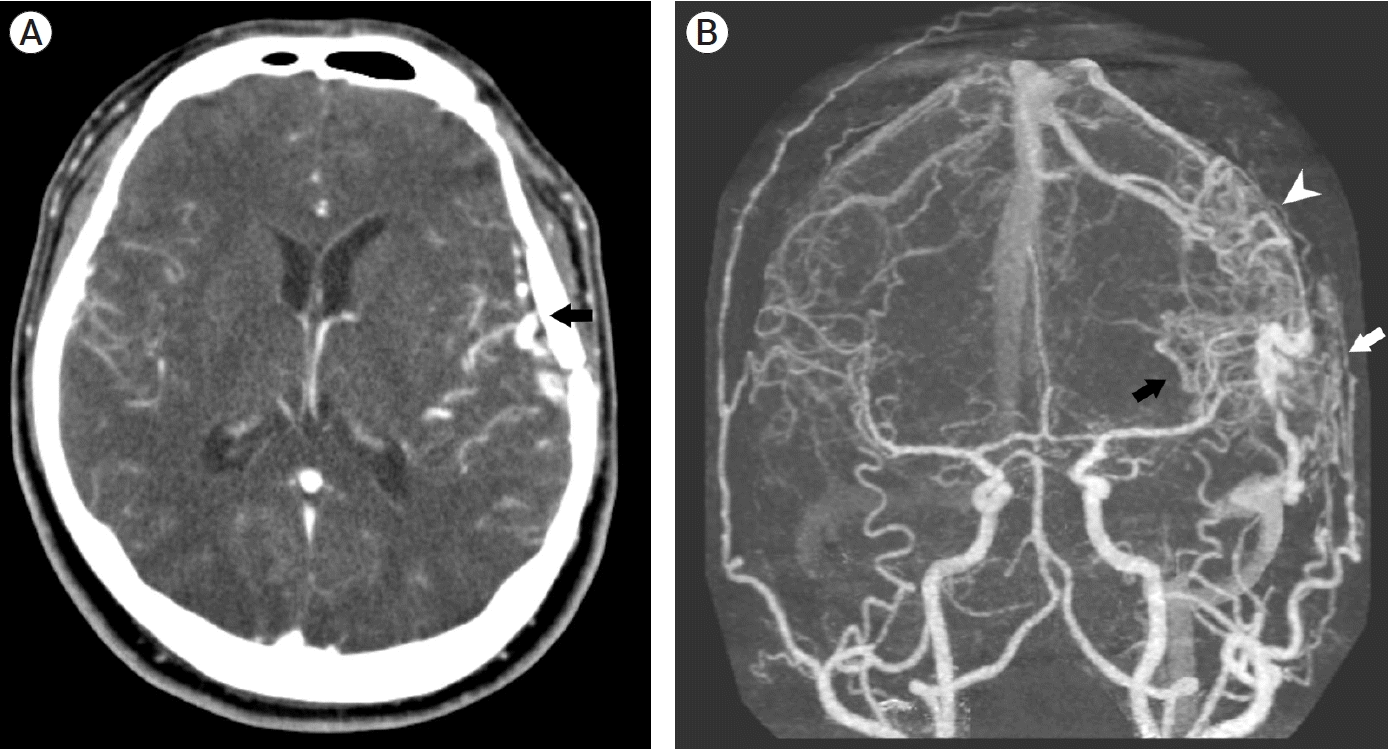

A 39-year-old man visited the neurosurgery department and presented with a left-sided pulsatile headache. The patient had a history of surgical clipping for a ruptured left anterior choroidal artery aneurysm using a conventional pterional approach 2 years previously. Computed tomography (CT) angiography revealed engorged tortuous cortical vessels near the previous craniotomy site and sylvian fissure, indicating a suspicious AVF which had not been detected on CT conducted 2-years before presentation (Fig. 1). Digital subtraction angiography (DSA) was performed for treatment planning, and external carotid angiography demonstrated a dural AVF fed by the branches of the middle meningeal artery (MMA) and superficial temporal artery (STA), draining directly into the engorged superficial middle cerebral vein (SMCV), vein of Labbe, and sigmoid sinus (Fig. 2A). Ectatic changes in the draining veins and cortical venous reflux were observed. Ipsilateral internal carotid artery angiography revealed additional multiple feeders arising from the middle cerebral artery (MCA), suggesting a mixed pial and dural AVF (Fig. 2B, C). Due to the difficulty of the transarterial approach through multiple small feeding arteries, transvenous coil embolization was performed via the sigmoid sinus and enlarged vein of Labbe (Fig. 3). Complete obliteration of the fistula was achieved, confirmed by postoperative DSA (Fig. 4), and the patient was discharged with no neurological complications.